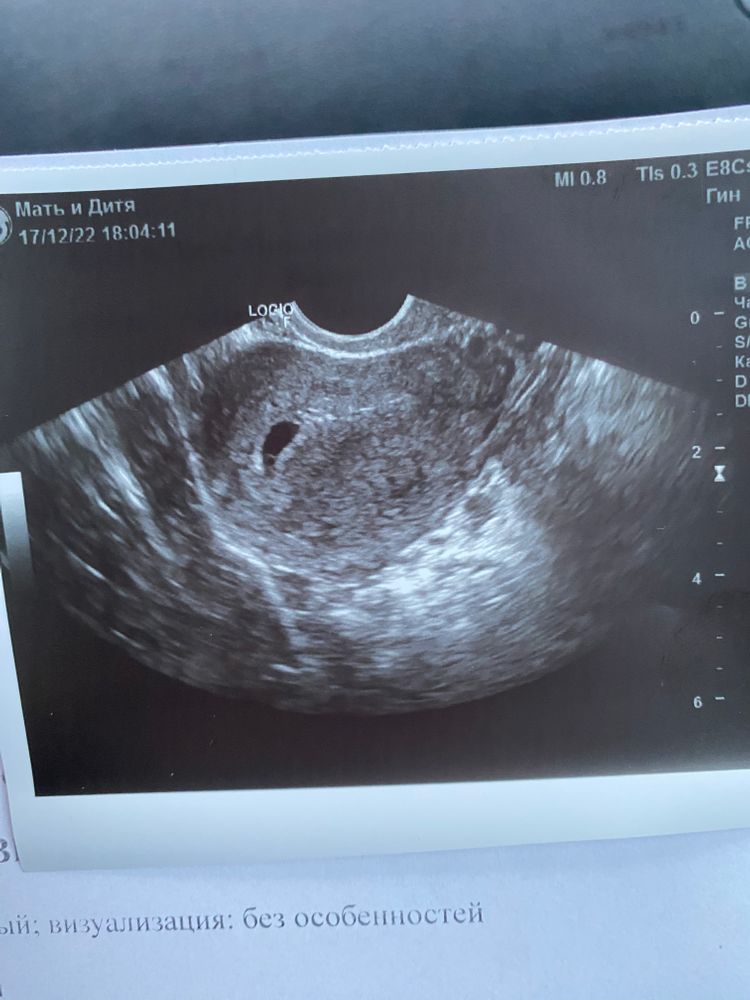

Посмотрели нас) Все хорошо 👌

Ни отслоек, ни гематом - ни-че-го!)

Вот наше чудо!) Да, один!